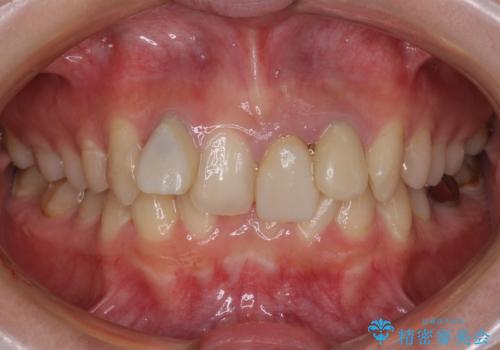

前歯綺麗にしたい。

変色してきた歯とプラスチックのクラウン オールセラミッククラウン治療